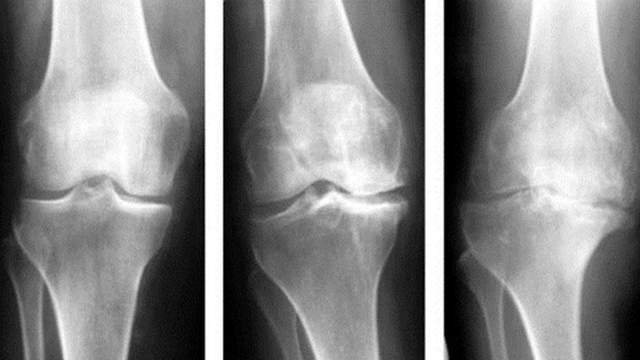

Артроз – це захворювання суглобів, викликане дегенерацією суглобового хряща. Воно спричиняє порушення рухливості суглоба, яке викликає неприємний біль.